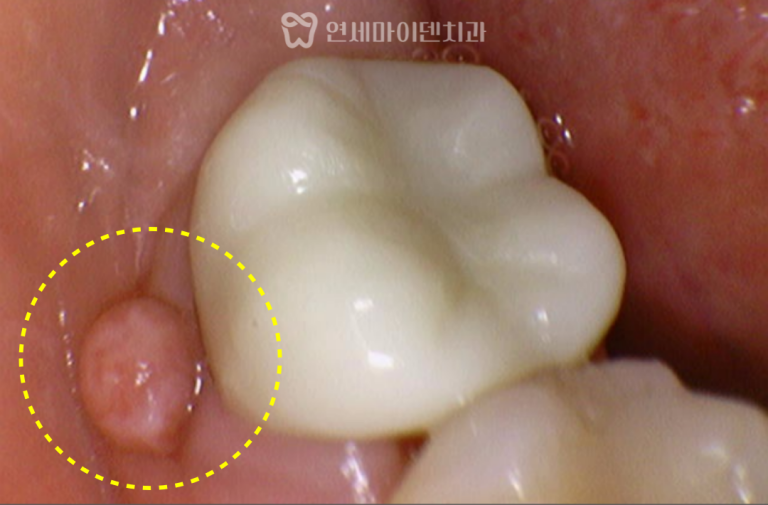

재신경치료&임플란트 증례: 잇몸 여드름 신경치료 후에도 치아 뿌리에 염증이 생기고,잇몸에 여드름 같은 고름 주머니가 올라오면,대부분 ‘발치해야…

안녕하세요, 소중한 치아를 지키는연세마이덴치과 닥터꼬집입니다. 많은 분들이 신경치료 후 염증이 재발했을 때,재신경치료를 시도할지, 임플란트로 바로 가는게…